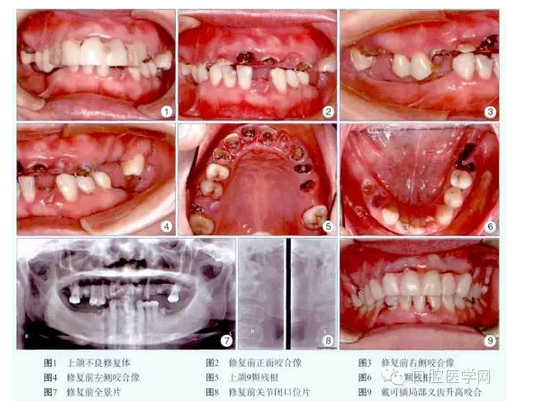

檢查:上前牙樹脂固定修復(fù),松動(dòng)。11、12、13、16、21、22、23、24、25、32、36、44、45殘根,叩痛(+),1度松動(dòng)。26、31、37、46、47缺失,牙槽嵴較豐滿。14、15、17、27、33、34、35、41、42、43齲齒,叩痛(-),松動(dòng)(-)。正中牙合位無牙合接觸,咬合垂直距離降低,息止牙合間隙6mm,張口度正常,無顳下頜關(guān)節(jié)彈響及觸痛,牙石I度,齦緣紅腫(圖1~6)。全景片示所有殘根根尖有透光區(qū),多數(shù)牙牙槽骨水平吸收約根長的1/4~1/3,可利用牙槽骨高度:16為12.5mm,24為14.9mm,26為11.0mm(圖7)。關(guān)節(jié)片未見明顯異常(圖8)。

診斷:①上頜不良修復(fù)體,②上下牙列缺損,③慢性牙周炎,④14、15、17、27、33、34、35、41、42、43齲齒,⑤11、12、13、16、21、22、23、24、25、32、36、44、45殘根。治療過程:術(shù)前拍全景片,關(guān)節(jié)片,取研究模,照數(shù)碼像,簽署知情同意書。潔牙,拔除11、16、22、24、25、36、44、45殘根。14、15、17、27、33、34、35、41、42、43用FiltekZ350納米樹脂(3M公司,美國)充填。膠托可摘局部義齒升高咬合4mm,重新建立新的頜位關(guān)系(圖9)。